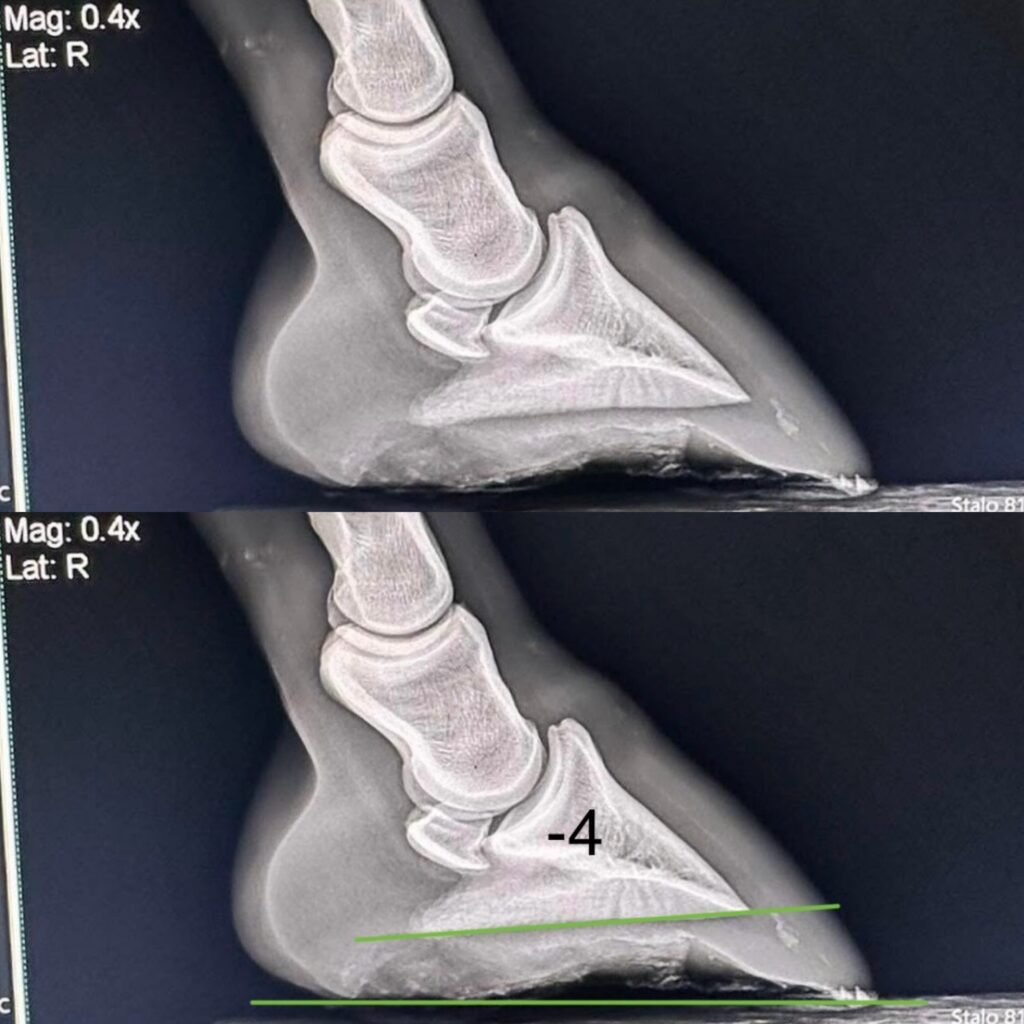

In bovenstaande foto zie je een hoef met typische kenmerken van NPA. Kun jij ze ontdekken?

Hier rechts en onder zie je röntgenfoto’s met verschillende hoeken. De onderste groene lijn is de grondlijn, de bovenste groene lijn is de onderkant van het hoefbeentje. De graden staan erbij aangegeven. Kijk maar hoe anders de gewrichten op elkaar gestapeld staan bij de verschillende hoeken!